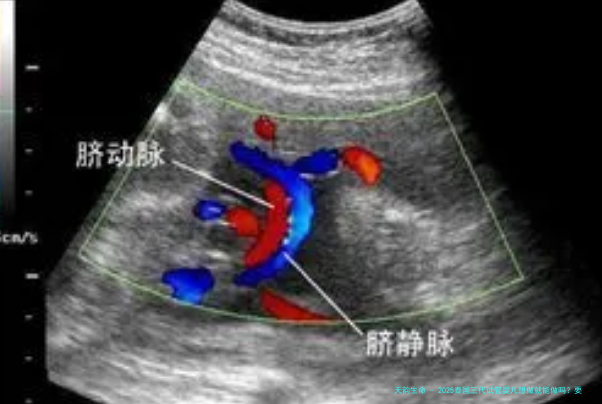

做泰国三代试管婴儿需要具备的身体条件,括女方不能有重大躯体疾病、重大脏器疾病,夫妇双方不能有严重心理疾病和不良嗜好等。而一些常见的不孕不育疾病,比如女方输卵管堵塞、子宫肌瘤、子宫内膜异位、卵巢囊肿,男方少精弱精、精子畸形、精液含有病毒,或夫妇双方染色体有异常的,都可以通过泰国三代试管婴儿获得自己的宝宝。